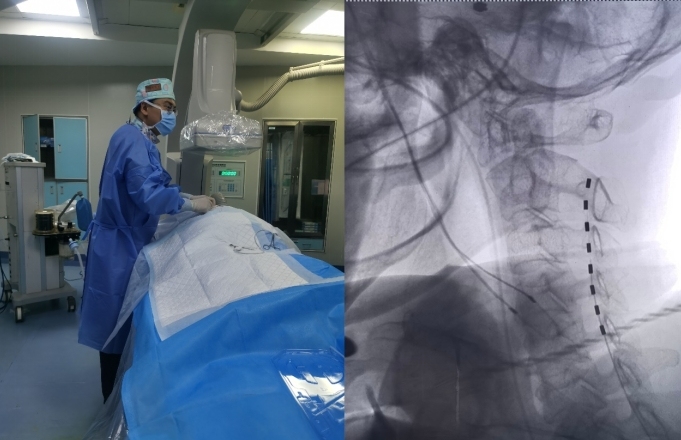

手術(shù)中,醫(yī)護團隊展現(xiàn)了極高的專業(yè)素養(yǎng)和技術(shù)水平,順利完成了手術(shù)流程。開啟測試模式后,在手術(shù)中調(diào)節(jié)電刺激參數(shù),李女士肌電圖顯示良好反應(yīng),雙側(cè)數(shù)據(jù)對比滿意。

脊髓電刺激技術(shù)是通過在患者脊髓附近植入電極,利用電刺激激活神經(jīng)系統(tǒng),改善神經(jīng)傳導(dǎo)和腦血流量,促進(jìn)神經(jīng)遞質(zhì)釋放,以達(dá)到喚醒患者的效果。